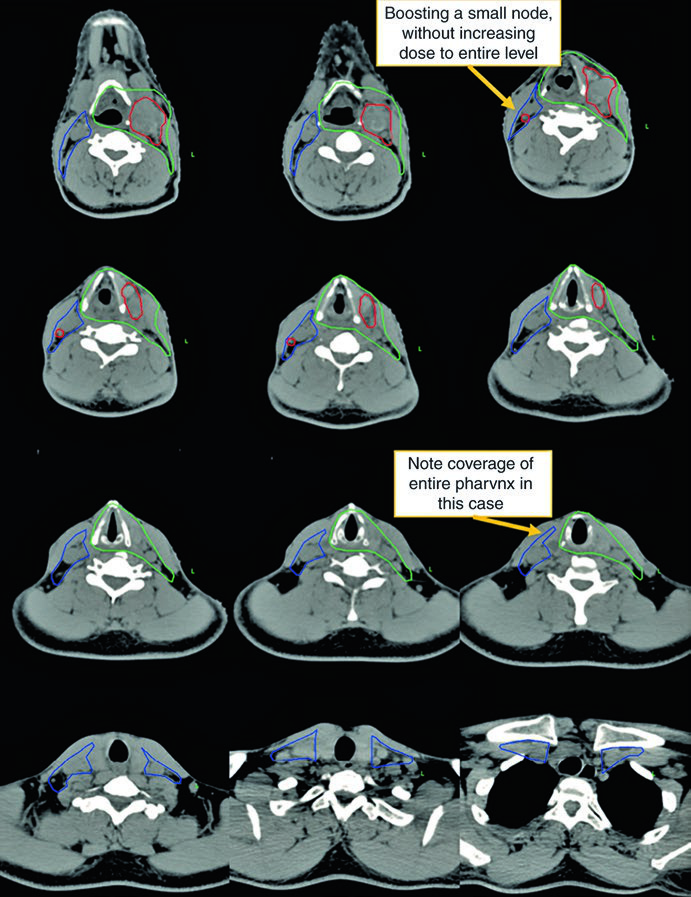

Observe a diferença entre o delineamento no pescoço operado (ipsilateral) e o contralateral. O CTV66Gy (vermelho) cobre o leito cirúrgico de alto risco; o CTV54-60Gy (verde) cobre as mucosas faríngeas em risco de abrigar o primário; e o CTV54Gy (azul) cobre o pescoço contralateral profilaticamente. Essa assimetria reflete o princípio de escalonar a dose conforme o risco real.

A visualização em cortes sagitais (Fig. 10.2) é particularmente útil para confirmar a extensão craniocaudal correta dos volumes de mucosa — nasofaringe, orofaringe e laringe/hipofaringe — e assegurar que não haja lacunas entre os CTVs adjacentes. O isocentro radiográfico serve como referência geométrica para o planejamento.

Neste caso, o CTV70Gy (vermelho) engloba a doença macroscópica bilateral; o CTV60Gy (verde) cobre as mucosas faríngeas em risco; e o CTV54Gy (azul) inclui todo o pescoço bilateral profilaticamente. A negatividade para HPV justifica a cobertura abrangente de toda a faringe, pois sem a orientação viral para um subsítio específico, o risco é distribuído ao longo de todo o eixo mucoso.

A presença de ECE neste caso reforça a indicação de quimioterapia concomitante. A dose de 70 Gy na doença macroscópica e 54–60 Gy nas mucosas em risco segue o escalonamento padrão. Compare essa abordagem com as estratégias específicas para câncer de laringe, onde o foco é preservar a função laríngea.